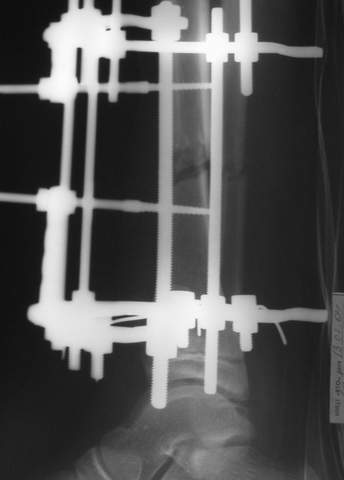

В аттачтах №№ 1 и 2 - примеры, когда 2 кольца не позволили послеоперационно

исправить смещение фрагментов большеберцовой (по ширине и вальгусное).

А казалось бы (#2) - поиграй на штангах и все влетит.

Оперировал не я

1

1a